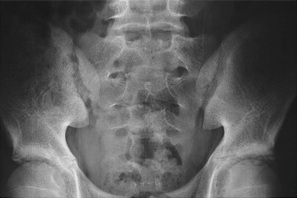

Smerterne i ryggen kan være udtryk for andre tilstande i ryggen, og derfor benytter lægen hyppigt billedundersøgelser i udredningen. En særlig MR-skanning af bækkenled og hele rygsøjlen vil kunne vise gigtforandringer tidligt i forløbet. Almindelige røntgenbilleder af bækkenled og rygsøjle viser ofte først forandringerne efter mange års sygdom.

Normal røntgen af bækkenled

Sammenvoksede bækkenled efter mange års sygdom